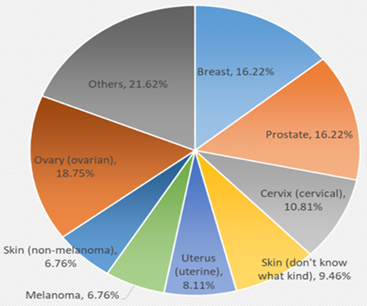

Patients with RA have a 1.64-fold [1.51–1.79] increased risk of developing lung cancer compared to the general population [4]. Tobacco is a risk factor for developing lung cancer and RA in predisposed populations, by inducing the production of anti-CCP antibodies [4]. Furthermore, chronic pulmonary inflammation due to rheumatism may explain this increase in lung cancer. Choi, reported in thier study that Overall, malignancies occurred in 170 (5.5%) and 662 (5.4%) participants in the RA group (n = 3070) and without the RA group (n = 12,280), respectively [8]. In the RA group, the five most commoncancers were lung, thyroid, gastric, colorectal, and hepatic cancer (1.77, 1.64, 1.59, 1.26, and 0.65 incidence rate per 1000 person-years, respectively) [8]. Thus, chondrosarcoma is classically very rarely reported as a solid cancer associated with rheumatoid arthritis (Figure 1). Hence the interest in presenting our observation.

Figure 1: Type of cancers for patients with rheumatoid arthritis [9].